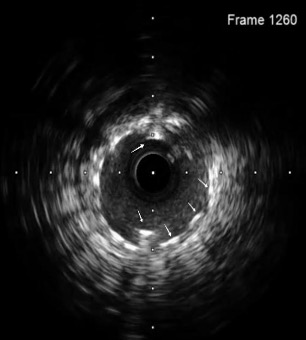

A coronary snare was used to retrieve the proximal segment of the retained wire. Partial extraction was achieved, but tangled wire fragments remained lodged in the proximal LAD. To stabilize these remnants, an additional DES was deployed to pin the wire against the vessel wall. Although angiography initially appeared satisfactory, intravascular ultrasound (OptiCross, Boston Scientific) proved pivotal by revealing that the wire loops had coiled within the stent, extended retrogradely into the proximal LAD, and reentered the stented segment near the left main stem (LMS) (Figures 2 [red arrow], 3A-C, Video 3).

A second DES (Resolute Onyx, Medtronic) was then deployed from the proximal LAD into the LMS, effectively jailing the wire fragments. IVUS assessment was performed from the ostial LAD (Figure 4A-C, Video 5).